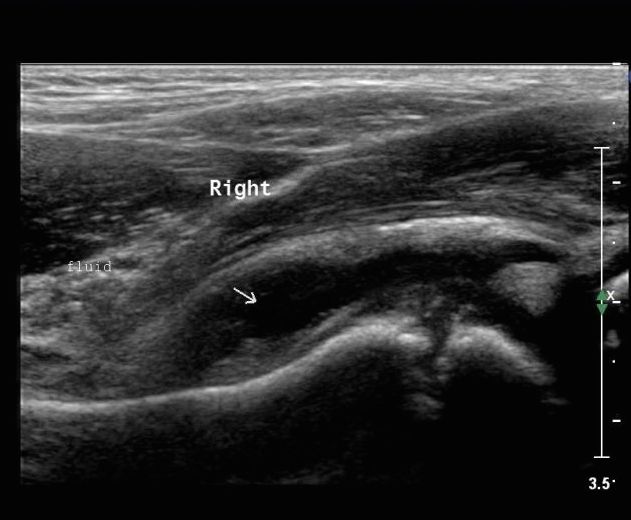

2. 초음파 소견

관절 주위 연부조직과 관절내 삼출액 유무를 확인할 수 있습니다. 대퇴 경부 전방에서 장요근의 후방까지의 거리를 측정하여 2mm 이상 증가한 경우를 활액 증가 소견으로 볼 수 있습니다.